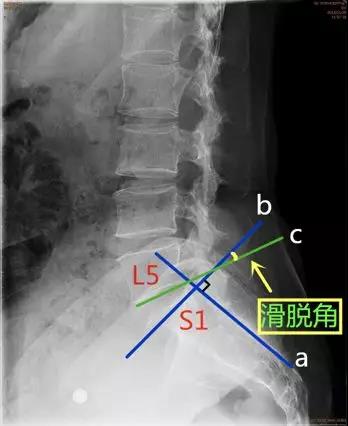

- 滑脱角:S1后缘垂线与L5下终板平行线之间的夹角。正常<10°。

临床意义:>10°提示滑脱进展的风险。